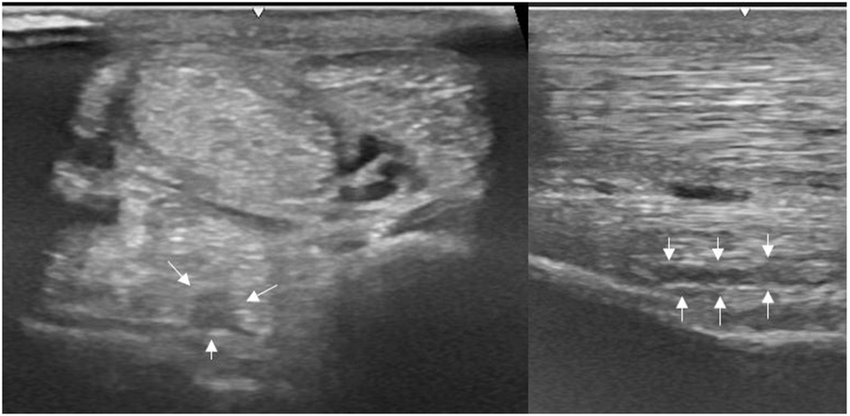

Transverse image of a proximal suspensory ligament grade 1 lesion about 4 cm distal to the head of the MTII. The lesion appears as a focal, well-defined, hypoechogenic area (white arrows) in the ligament occupying <25% of the cross-sectional areal. Longitudinally the lesion is well-demarcated (white arrows), it begins from the insertion and extends distally. In transverse image medial is to the left; in longitudinal image proximal is to the left. Kendra D. Freeman et al 2025